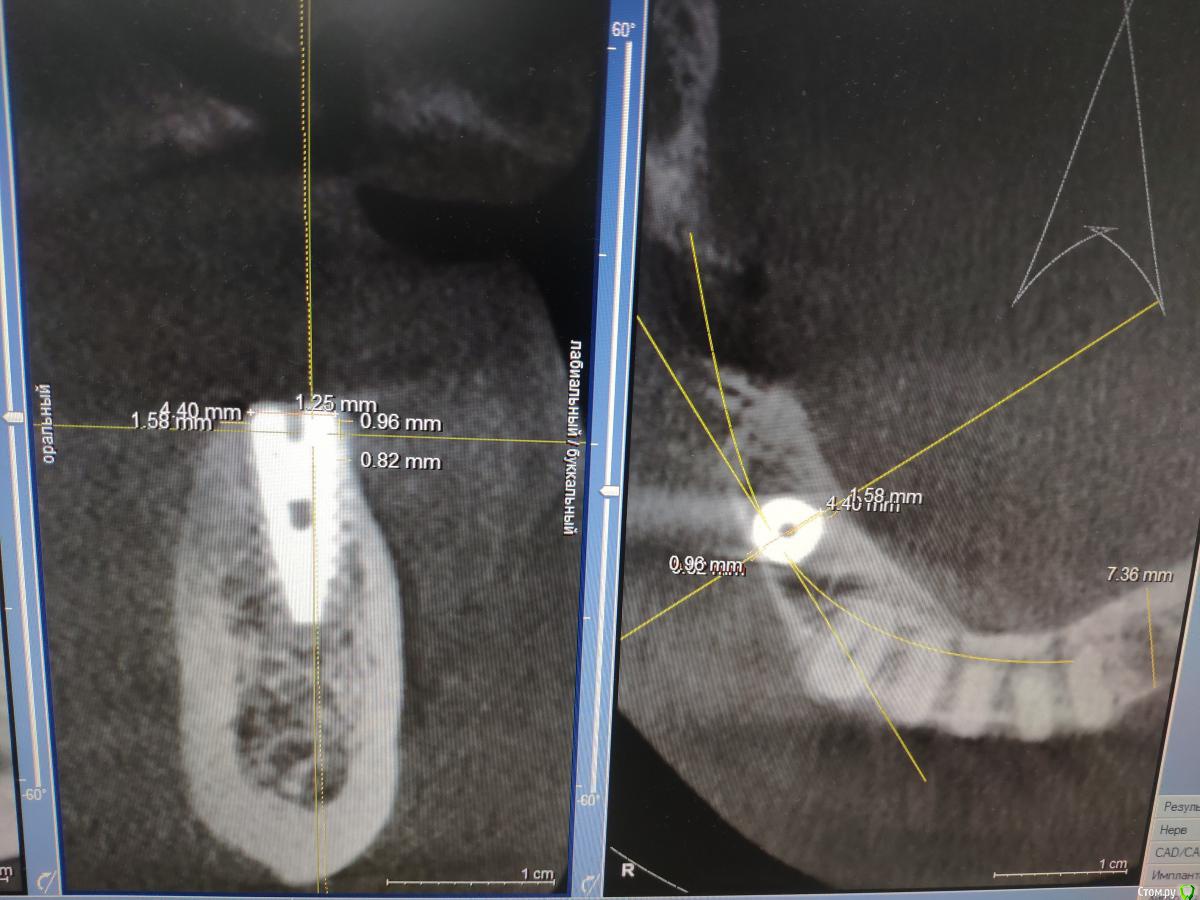

zumanok Опубликовано 11 декабря, 2019 Поделиться Опубликовано 11 декабря, 2019 Здравствуйте доктора, установлен имплант 5 недель назад. 4.2 на 11.5 Область 3.4. сделать проверочное КТ не было возможности. На новом снимке обнаружилось что увел имплантат щечнее чем планировал и стенка меньше 1мм (на фото самая тонкая стенка). Так же отмечено что имплант несного фонит.Как вы посоветуете? 1.Убрать и переставить сразу немного медиальнее(но слабо себе представляю) или Переставить через 2 месяца. 2. Оставить так. Благодарю за советы Ссылка на комментарий

krokomot Опубликовано 11 декабря, 2019 Поделиться Опубликовано 11 декабря, 2019 позиция имплантата неверная, переставить медиальнее, заглубить, лучше сразу, через 2 месяца получите интегрированный имплантат. 2 Ссылка на комментарий

zumanok Опубликовано 11 декабря, 2019 Автор Поделиться Опубликовано 11 декабря, 2019 позиция имплантата неверная, переставить медиальнее, заглубить, лучше сразу, через 2 месяца получите интегрированный имплантат.Сейчас понимаю что подвинуть медиально не получится, только угол поменять немного, т.к. корень соседа мешает.При этом не смогу сразу зафиксировать. Ссылка на комментарий

diesel87 Опубликовано 11 декабря, 2019 Поделиться Опубликовано 11 декабря, 2019 Сейчас понимаю что подвинуть медиально не получится, только угол поменять немного, т.к. корень соседа мешает.При этом не смогу сразу зафиксировать. Для позиции премоляра расстояние до клыка очень большое, нужно переставить имплант с медиальным наклоном по оси клыка и заглубить еще, возможно стоит взять имплант длинной 10 мм, не вижу точного расстояния до ментального. Ссылка на комментарий

diesel87 Опубликовано 11 декабря, 2019 Поделиться Опубликовано 11 декабря, 2019 А через сколько переставляете? Не думаю что получится сразу поставить новый.Есть все условия чтоб поставить сразу, чуть пересверлиться нужно медиальнее под углом, но если сомневаетесь в своих навыках то тогда идти по классике с ожиданием минимум в 6-8 недель. 1 Ссылка на комментарий

колесников Опубликовано 12 декабря, 2019 Поделиться Опубликовано 12 декабря, 2019 (изменено) О святые профыесора! Да идеально стоит ваш имплант! Ориентируйте ангуляцию и положение на дистальный имплант ,а не на клык. Сст с фдм и отпустите пациента. Изменено 12 декабря, 2019 пользователем колесников 2 Ссылка на комментарий